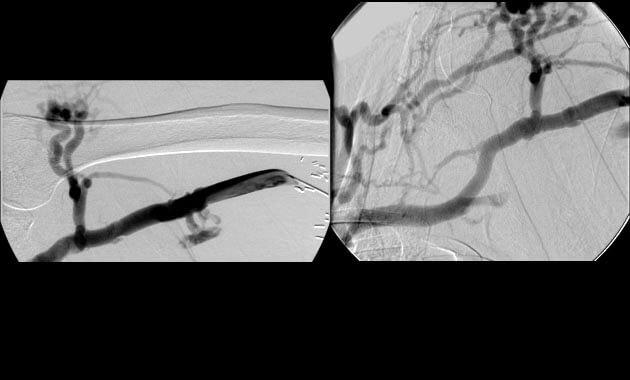

Portal Hypertension

- Conditions: Portal hypertension, esophageal varices, gastric varices, variceal bleeding, ascites, portal vein thrombosis, Budd-Chiari syndrome

- Services: Transjugular intrahepatic portosystemic shunt (TIPS), Balloon-assisted retrograde transvenous obliteration (BRTO), portal vein recanalization, paracentesis, abdominal PleurX placement